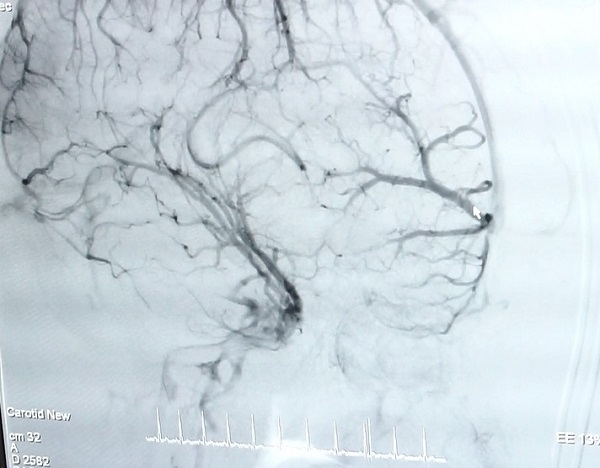

Hình ảnh mạch máu não của bệnh nhân N.

Kết quả chụp CT não tại Bệnh viện Quốc tế City cho thấy, bệnh nhân bị xuất huyết não thái dương trái – não thất nghi ngờ do vỡ dị dạng mạch máu não. 14h00 ngày 22/03/2019, bệnh nhân được TS.BS Trần Chí Cường, cố vấn chuyên môn tại Trung tâm Đột quỵ CIH-SIS Bệnh viện Quốc tế City chụp mạch máu não bằng ứng dụng công nghệ cao – DSA nhằm phát hiện những bất thường của mạch máu.

Theo TS.BS Trần Chí Cường, dị dạng mạch máu (AVM) vô cùng nguy hiểm bởi có thể gây ảnh hưởng đến chi phối của não bộ lên hoạt động cơ thể, nếu phát hiện và điều trị muộn có thể dẫn đến tử vong. Bệnh nguy hiểm nhưng nếu được chẩn đoán sớm có thể điều trị khỏi hoàn toàn. Hiện nay, phương pháp chụp mạch máu não bằng ứng dụng DSA giúp bác sĩ có cái nhìn chính xác về vị trí, kích thước, hình dạng của đoạn mạch dị dạng đồng thời vẽ được biểu đồ huyết mạch nơi mạch máu dị dạng phát sinh.